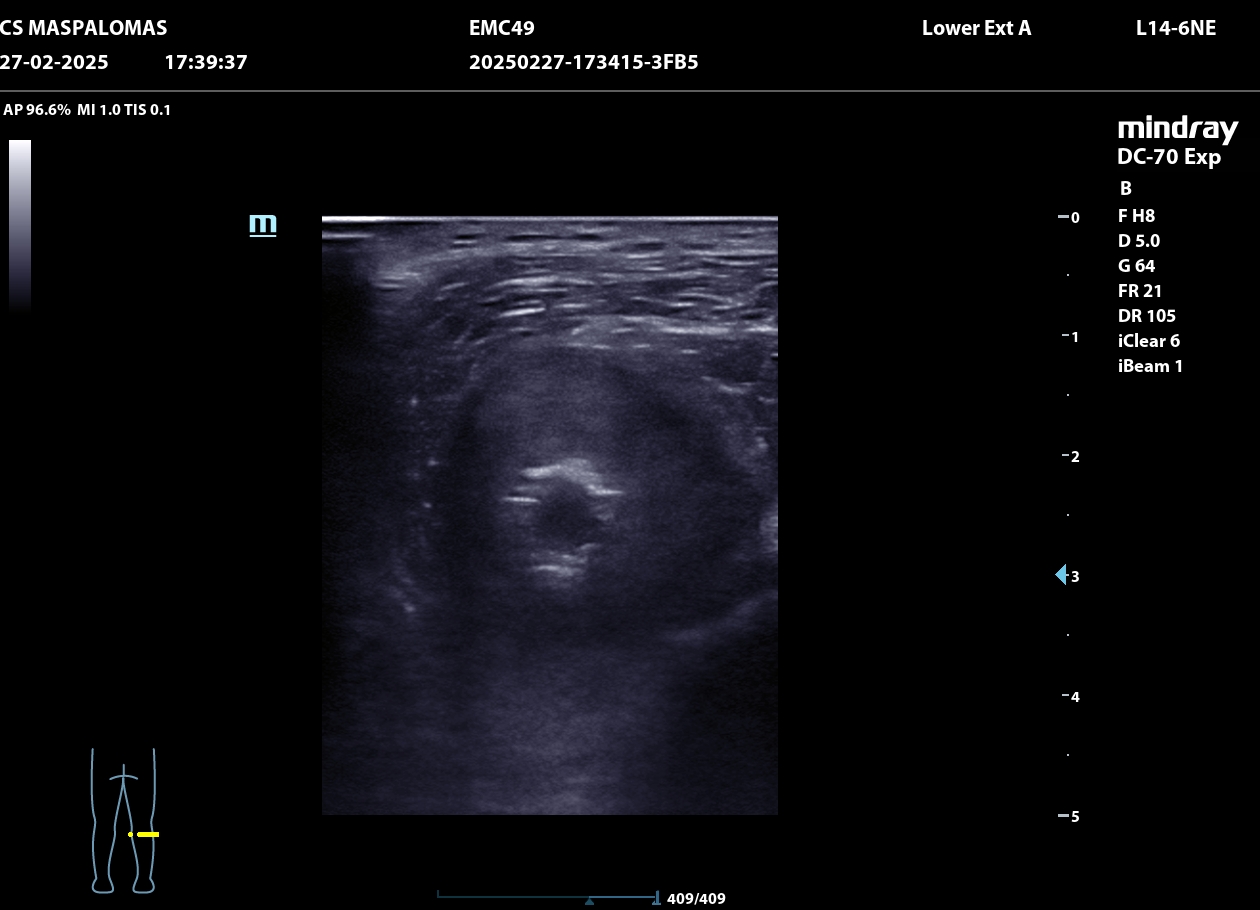

Se realiza ecografía clínica en consulta que revela un aneurisma de la arteria poplítea derecha de 4,66 cm con trombo intraluminal de gran tamaño.